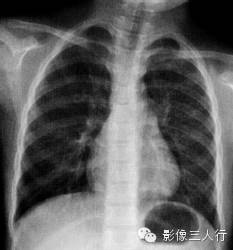

报告示范:双肺肺纹理增强,左肺门影增大。胸廓对称,纵隔、气管居中。心脏形态、大小、位置正常。双侧膈肌光滑,肋膈角锐利(图2)。

图2胸内淋巴结结核(男患,8岁,咳嗽半个月)

(A)正位